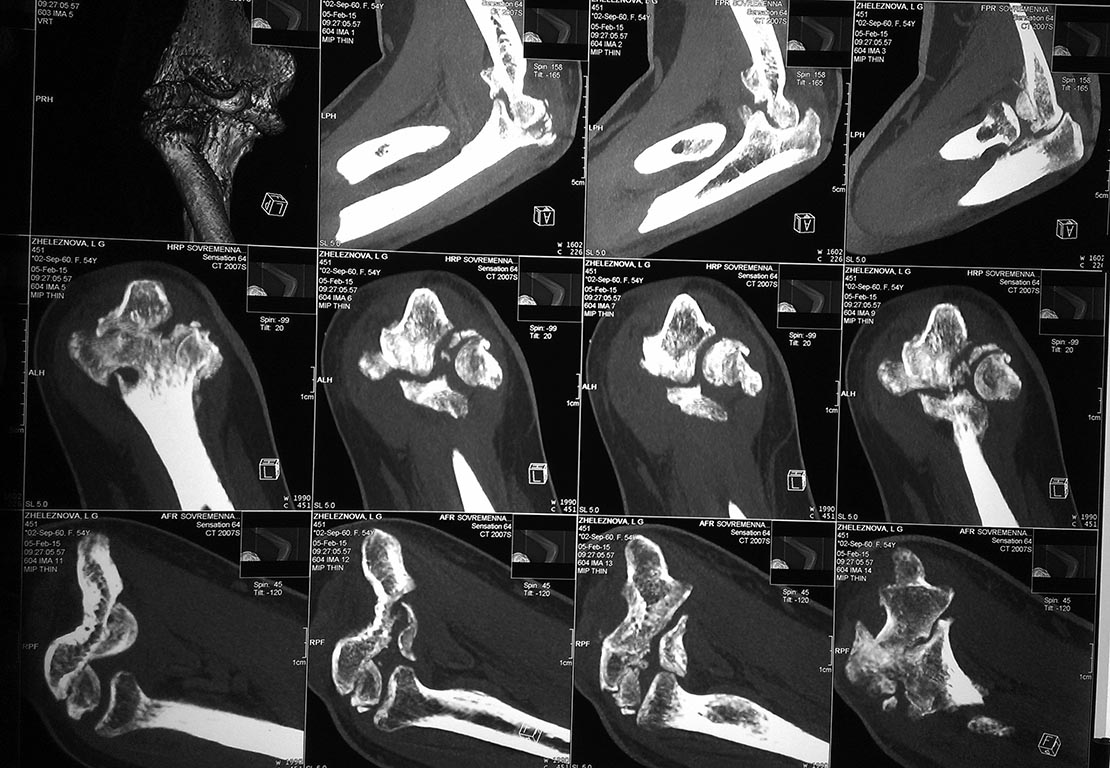

У женщины 54 лет имеются последствия закрытого вывиха костей предплечья...

Травма 08.11.14 г., окончательное вправление лишь 10.11.14 г., тогда же появились признаки нейропатии локтевого нерва, они остаются до сих пор.Движения в суставе качательные, практически анкилоз в положении 90 град.

Снимки КТ в приложении.